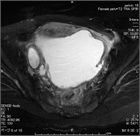

1. 下腹部痛・発熱・炎症反応上昇・膿瘍など画像所見・原因病原体の検出をもって診断する。